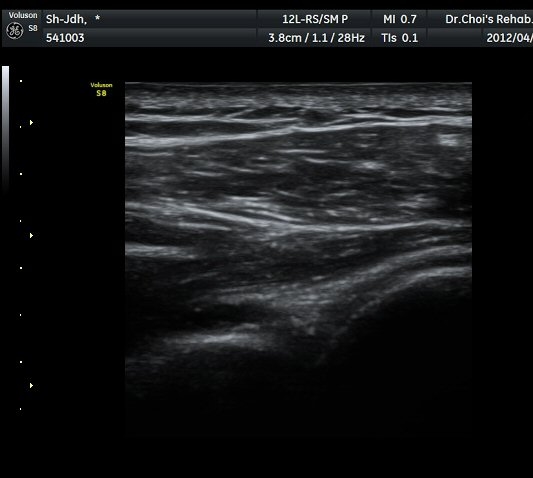

À̵ιڱ٠Ⱦ´Ü¸é°Ë»ç¿¡¼­ À̵ιڱٰÇÀÇ ºñÈĸ¦ º¸ÀÓ(»çÁø 1, 2).

À̵ιڱٰú ÀÌ¿ôÇÑ °ß°©ÇÏ±Ù°Ç »óºÎ¿¡¼­ ±¹¼ÒÀûÀÎ ¿¬°á¼º ¼Ò½ÇÀÌ °üÂûµÊ(»çÁø 3).